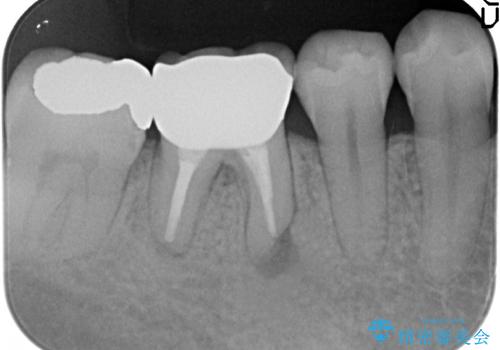

オールセラミッククラウン 歯茎から膿が出る歯の治療

- 数か月前から右下の奥歯の歯茎から膿が出る、他院で相談したところ抜歯といわれたが何とか残せないか診て欲しいといらっしゃった方の症例です。

再根管治療を行い、フィステル(膿の出口)の消失および根尖病変の縮小を確認後、オールセラミッククラウンによる補綴を行いました。

- オールセラミッククラウン…¥100,000、仮歯…¥10,000、ファイバーコア…¥20,000、精密根管治療費別途費用は治療当時の料金となります